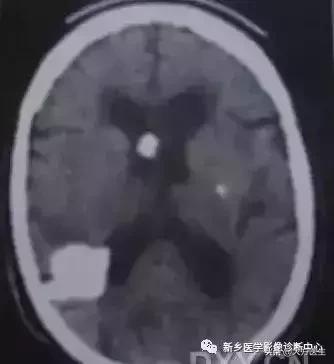

6、颅内动脉瘤

20岁以下及70岁以上多见。一般无明显症状,有时表现为视野缺损,颈内动脉海绵窦处瘤可有颅神经及眼神经损害症状。

CT:平扫为圆形稍高密度影,边清,明显均匀强化,有血栓时,血流部为稍高密度,血栓为等密度,且不强化。无血栓时,MR T1、T2均无信号流空影,有血栓时多为层状高低相间混杂信号。